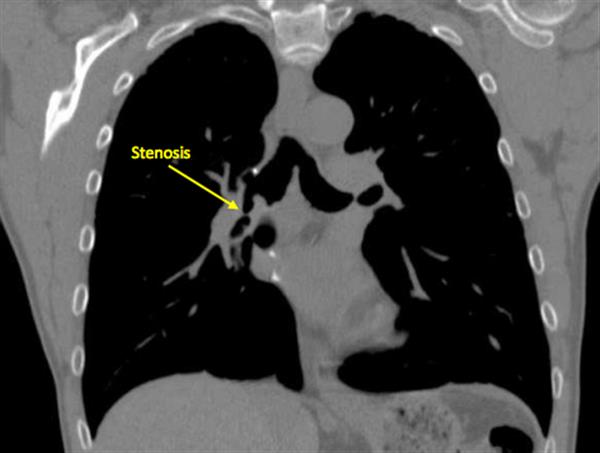

3D打印技術在醫療應用上的價值有目共睹。法國醫生近日利用3D打印技術打印模具,製作定制化支氣管,並完成支氣管植入手術,成為全球首例。

這個定制的支氣管由法國圖盧茲CHU醫院與3D打印公司Anatomik Modeling聯手打造,他們透過用儀器掃描出病人支氣管的3D圖,3D打印出支氣管模具,並用模具製作出植入病人體內的矽膠定制支氣管。

這個模具精確地顯示出患者的支氣管形狀,故製作出來的支氣管百分百適合植入病人體內,目前患者的恢復狀況良好。